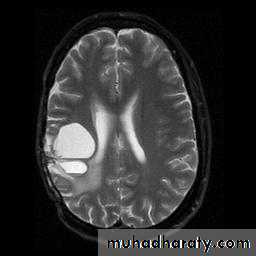

T2 WEIGHTING

A long TR and long TE will result in a T2 weighted image

Excellent for demonstrating pathologyMANY OTHER DIFFERENT TYPES OF IMAGES THAT COMBINE ABOVE AND INCLUDE OTHER PARAMETERS

Brain Tumor Imaging

T2-weighted Axial